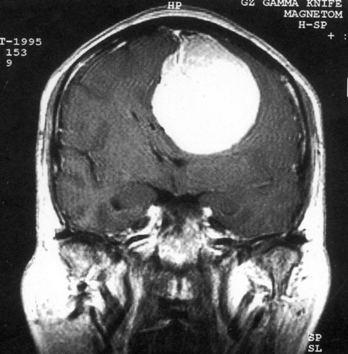

问题 病历摘要:??患者,男,40岁。发作性左下肢抽搐1年余,每次发作3~5分,每周发作1~2次。每次发作后感左下肢乏力,约半日后可自行恢复。既往身体健康。体检:神清,头顶部偏右有局限性骨性隆起(1.5×1.5cm),左鼻唇沟稍浅,伸舌居中。感觉、运动无明显异常。左浅反射减退,左下肢腱反射稍亢进,左Babinski征(-)。 术后处理包括下列哪些措施?提示:肿瘤病理报告为脑膜瘤